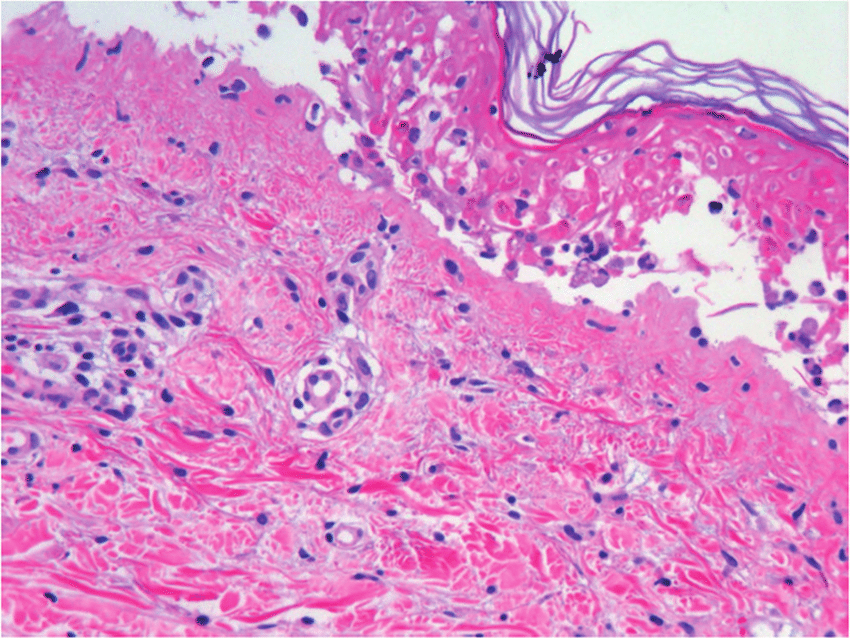

En esta revisión sistemática y metanálisis de todas las series de casos, los antibióticos se asociaron con más de una cuarta parte de los casos de síndrome de Stevens-Johnson y la necrólisis epidérmica tóxica descritos en todo el mundo. La clase de sulfonamida se asoció con el 32 % de los casos, seguida de las penicilinas (22 %), las cefalosporinas (11 %), las fluoroquinolonas (4 %) y los macrólidos (2 %). Estos hallazgos resaltan la importancia de la administración de antibióticos, la educación y la concientización de los médicos, y sopesar la evaluación de riesgo-beneficio de la elección y duración de los antibióticos. JAMA Dermatol. 15 de febrero de 2023

En esta revisión panorámica, se buscaron publicaciones que abordaran los avances recientes en el diagnóstico y el tratamiento de la enfermedad. Debido a la naturaleza rara de la enfermedad, hay una falta de ensayos controlados aleatorios prospectivos y realizarlos en el futuro proporcionaría información valiosa sobre el manejo de esta enfermedad. Medicina (Kaunas), 28 de agosto de 2021